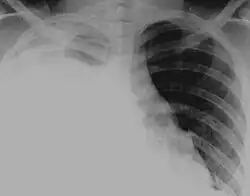

Hydrothorax is the synonym of pleural effusion in which fluid accumulates in the pleural cavity. This condition is most likely to develop secondary to congestive heart failure, following an increase in hydrostatic pressure within the lungs. More rarely, hydrothorax can develop in 10% of patients with ascites which is called hepatic hydrothorax. It is often difficult to manage in end-stage liver failure and often fails to respond to therapy.